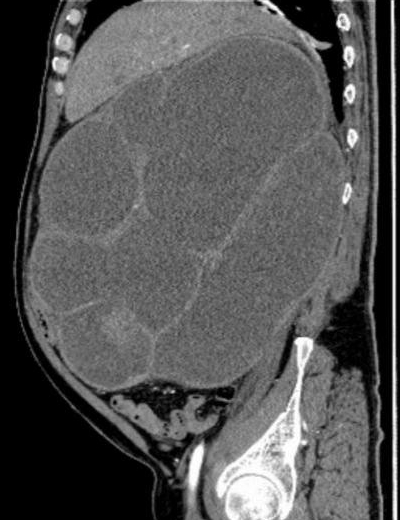

入院后,科室为患者完善影像学、内镜及病理等一系列检查,明确诊断其右肾盂、右输尿管及膀胱均存在恶性肿瘤病灶,其中右输尿管肿瘤引发梗阻,导致右肾严重积水,肾脏体积达650px×500px×175px,病情复杂程度远超常规病例,常规治疗方案难以达到理想疗效。

该手术的实施存在多重技术难点:肿瘤病灶累及右肾、右输尿管、膀胱多个脏器,且肿大的肾脏与周围血管、肠道等重要组织毗邻紧密、粘连严重,腹腔镜下操作空间狭小,对微创操作的精准度要求极高,操作不当极易引发大出血、脏器穿孔等严重并发症;手术涉及多脏器联合切除,步骤繁琐,对手术团队的配合度和操作连贯性要求严格;左侧输尿管皮肤造口术的实施直接关系患者术后排尿功能和生活质量,对手术的精细度、规范性有着高标准要求。

2026年1月底,患者完成新辅助治疗后,经评估手术条件已成熟,且患者及家属手术意愿明确。在麻醉科、手术室护理团队的全力配合下,李化升主任带领手术团队开始手术。为建立有效操作空间,团队先为患者穿刺抽出3600ml血性尿液,使肿大的肾脏体积有所缩小,随后开展腹腔镜下右肾切除操作。术中发现肾脏与十二指肠等周围组织严重粘连,腔镜下仅能游离约85%,团队随即调整方案,通过开放手术游离剩余部分并顺利取出肾脏。